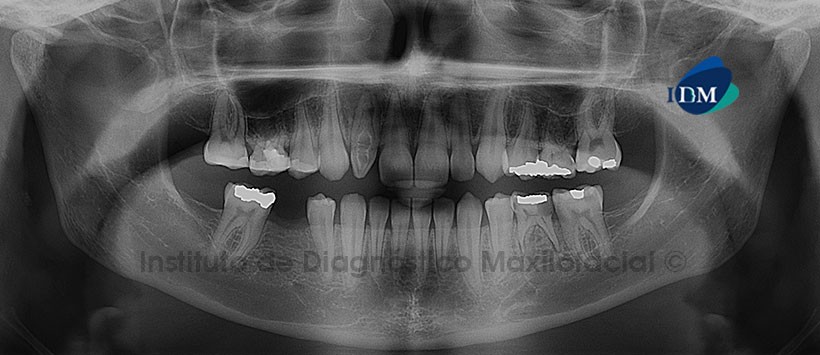

Paciente femenino de 17 años de edad que es referida para la evaluación imagenológica previa al tratamiento odontológico. La radiografía panorámica nos muestra múltiples restauraciones coronarias, presentando la pieza 75 una lesión de caries recidivante con probable compromiso pulpar. Se evidencia también la persistencia de las piezas 55, 65 y 75; así como, la ausencia de varias piezas permanentes. Por otro lado, lo que más llama la atención es la pieza 12 que presenta una alteración en la morfología dentaria caracterizada por la invaginación del tejido adamantino y dentinario hacia la cámara pulpar; signos radiográficos compatibles con Dens in Dente. (Fig. 1).